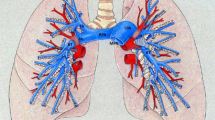

Patient-specific computational models could aid in planning interventions to relieve pulmonary arterial stenoses common in many forms of congenital heart disease. We describe a new approach to simulate blood flow in subject-specific models of the pulmonary arteries that consists of a numerical model of the proximal pulmonary arteries created from three-dimensional medical imaging data with terminal impedance boundary conditions derived from linear wave propagation theory applied to morphometric models of distal vessels. A tuning method, employing numerical solution methods for nonlinear systems of equations, was developed to modify the distal vasculature to match measured pressure and flow distribution data. One-dimensional blood flow equations were solved with a finite element method in image-based pulmonary arterial models using prescribed inlet flow and morphometry-based impedance at the outlets. Application of these methods in a pilot study of the effect of removal of unilateral pulmonary arterial stenosis induced in a pig showed good agreement with experimental measurements for flow redistribution and main pulmonary arterial pressure. Next, these methods were applied to a patient with repaired tetralogy of Fallot and predicted insignificant hemodynamic improvement with relief of the stenosis. This method of coupling image-based and morphometry-based models could enable increased fidelity in pulmonary hemodynamic simulation.